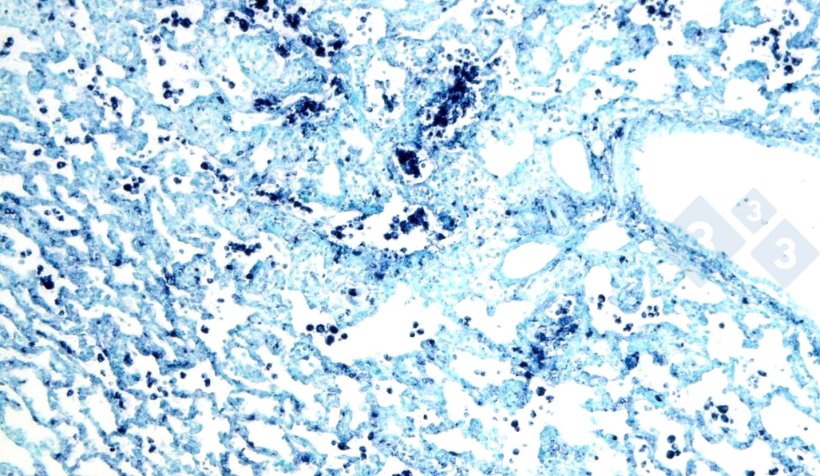

Najczęściej stosowanymi są immunohistochemia (ryc. 3) i hybrydyzacja in situ (ryc. 4), które umożliwiają wykrywanie patogenów w miejscu ich występowania, potwierdzając ich rolę w kontekście klinicznym i patologicznym. Ponadto istnieją inne techniki (barwienia histochemiczne), które nie wystarczają do ustalenia konkretnej etiologii, ale są w stanie wskazać przyczynę (np. barwienie Groccota w celu wykrycia grzybów lub barwienie Grama w celu wykrycia bakterii Gram-dodatnich lub Gram-ujemnych).